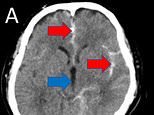

A CT scan (pictured) showed the man’s brain bleed. The white material indicated by red arrows is fresh blood that should not be present. Those spaces should be filled by cerebrospinal fluid, which looks like area marked by the blue arrow

Medics carried out a CT scan on his brain, to find the root cause of his symptoms.

Results revealed he had endured a subarachnoid haemorrhage – a life-threatening type of stroke that was caused by a blood vessel in his brain rupturing.